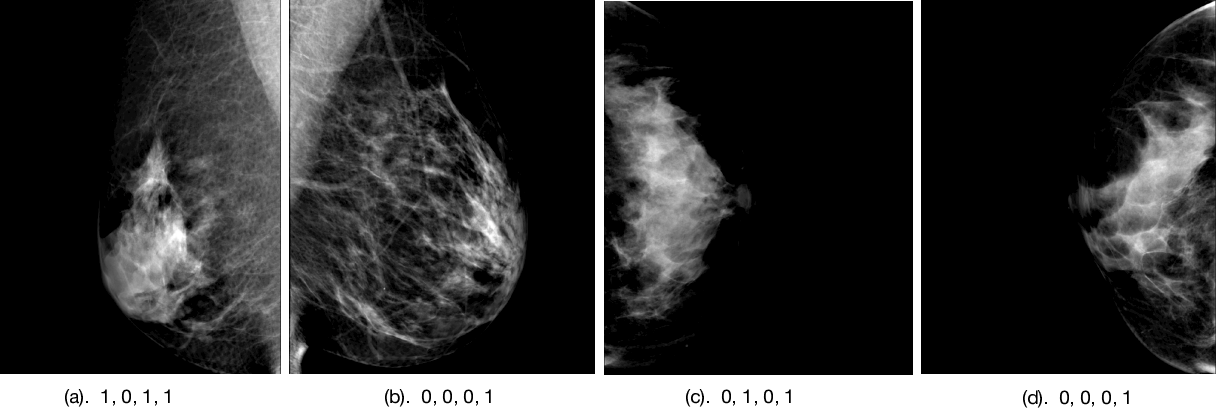

We further analyze this most successful classifier’s results before and after adding the radiologist gist response to the input vector. We notice interesting trends when comparing the radiologists’ decisions to the classifier’s decisions. The classifier utilizing both the deep features and the radiologist gist input manages to correct 8 of the 16 false negative errors that the radiologists made, while only introducing three false positives and one false negative. On the other hand, after introducing the radiologist gist input to the classifier, 25 errors made by the classifier without gist response input are corrected, with only three errors introduced. These corrections include 8 false negatives and 17 false positives. There are also 5 instances in which both the classifier and the radiologists make the same mistake (see Supplementary materials for these image samples). In this same case, we see an improvement over the classifier not utilizing radiologist gist response, increasing AUC from 0.681( CI [0.558, 0.789]) to 0.899( CI [0.823, 0.962]). One-way Welch’s F test shows a statistically significant main effect of the classifier on the AUC ( = , ). A Games-Howell post-hoc test revealed that the AUC of the classifier without gist input is statistically significantly lower than the radiologists’ gist response (0.679 +/- 0.0597, ), and that the classifier with gist input was statistically significantly higher than the radiologists’ gist response(, ).

Figures 4, 5, and 6 show the imaging for which both humans and CNNs make mistakes, model introduced errors, and model corrected human errors. Figure 7 shows the receiver operating characteristic curve (ROC curve) for each of the 16 end-to-end models between the CNNs and radiologist gist plus CNNs. Tables 1 and 2 show the AUC data and differences used in the main text from the 16 conditions we have tested. Although the present work provides knowledge about adding radiologists’ data into CNN, it does not allow for training on new data, thus restricting our application domain to a small range of in-house data.